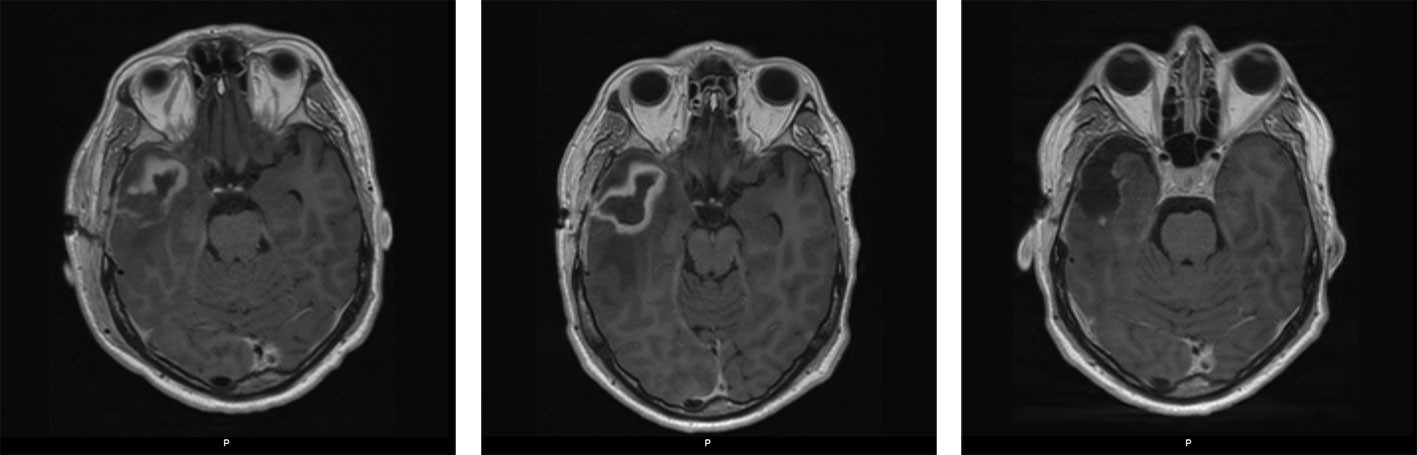

To dager senere sluttet kateteret å fungere, og pasienten fikk et nytt tilsvarende kateter via venstre overekstremitet. Prosedyren var ukomplisert, men kontroll-røntgen toraks viste unormalt leie av kateteret på venstre side av sternum (figur 2). CT toraks med intravenøs kontrast samme kveld viste at kateteret lå i en persisterende venstre vena cava superior, se figur 3a og figur 3b. Grunnet kontrastartefakter på bildene kunne man ikke da si sikkert om denne venen munnet ut i venstre eller høyre hjertehalvdel. Det gikk lett å aspirere blod og å injisere saltvann, og man tolket det som at kateteret fungerte normalt. Pasienten reiste hjem samme kveld i god form.

Persisterende venstre v. cava superior er den vanligste medfødte anomalien i venesystemet i toraks. Forekomsten i befolkningen er antatt å være ca. 0,3 % og 4–10 % hos pasienter med medfødt hjertesykdom (11–13).

Overkroppens venedrenasje kommer fra de embryologiske fremre kardinalvenene (figur 4) (11, 14–17). Ved normal utvikling anastomoserer disse omkring gestasjonsuke 8. Venstre kardinalvene går i regress til Marshalls ligament, og distale del blir til sinus coronarius. Høyre kardinalvene blir til v. cava superior. Persisterende venstre v. cava superior forekommer ved manglende regress av venstre kardinalvene og er assosiert med anomalier knyttet til sinus coronarius (12, 14) (figur 5). I 65 % av tilfellene er venstre v. brachiocephalica (også kalt tverrvene i denne artikkelen) fraværende (18). Vår pasient hadde åpen tverrvene (figur 3).

Ved regranskning av CT toraks tatt ved første innleggelse på universitetssykehus så man at pasienten hadde en persisterende venstre v. cava superior. Det ble nå bekreftet at denne munnet ut i venstre atrium.

Hos 90 % av tilfellene med persisterende venstre v. cava superior drenerer denne til høyre atrium via sinus coronarius. Disse er gjerne asymptomatiske og oppdages tilfeldig ved bildediagnostikk, sentralvenøs kateterisering eller kirurgi (11). De resterende 8–10 % drenerer direkte til venstre atrium via anomalier i sinus coronarius og skaper en høyre-til-venstre-shunt. Disse er assosiert med hjerneabscesser og tromboemboliske hendelser (12).

Persisterende venstre v. cava superior bør mistenkes dersom røntgen toraks viser sentralvenøst kateter på venstre side av mediastinum. Hvis anomalien ikke er godt kartlagt og man ikke kan utelukke en shunt, bør kateteret fjernes i påvente av dette (21). Ved erkjent persisterende venstre v. cava superior som drenerer til venstre atrium frarådes å legge venstresidig sentralvenøs tilgang (12). Påvises anomalien tilfeldig og videre utredning viser at den munner ut i venstre atrium, anbefales profylaktisk lukking (11–13). Dette gjøres enten ved hjelp av endovaskulære teknikker, som hos vår pasient, eller kirurgisk (22).